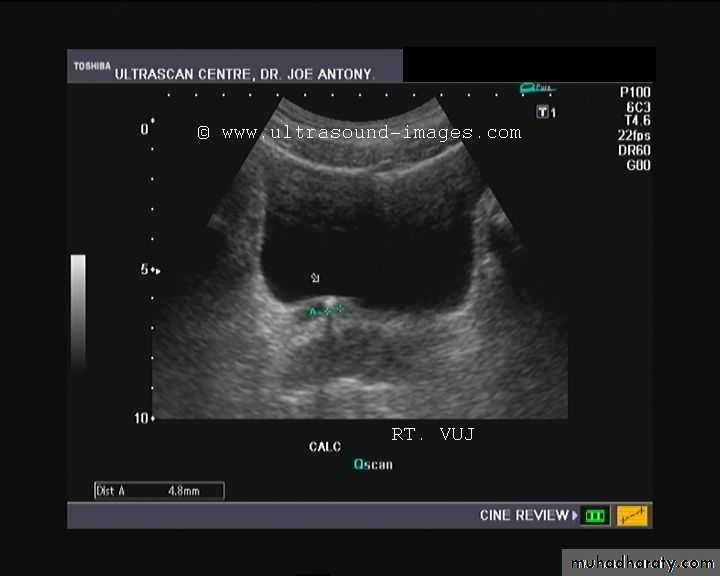

Urinary calculi

Nephrocalcinosis

Deposition of calcium salts in the medulla or cortex of the kidney.Medullary Nephrocalcinosis